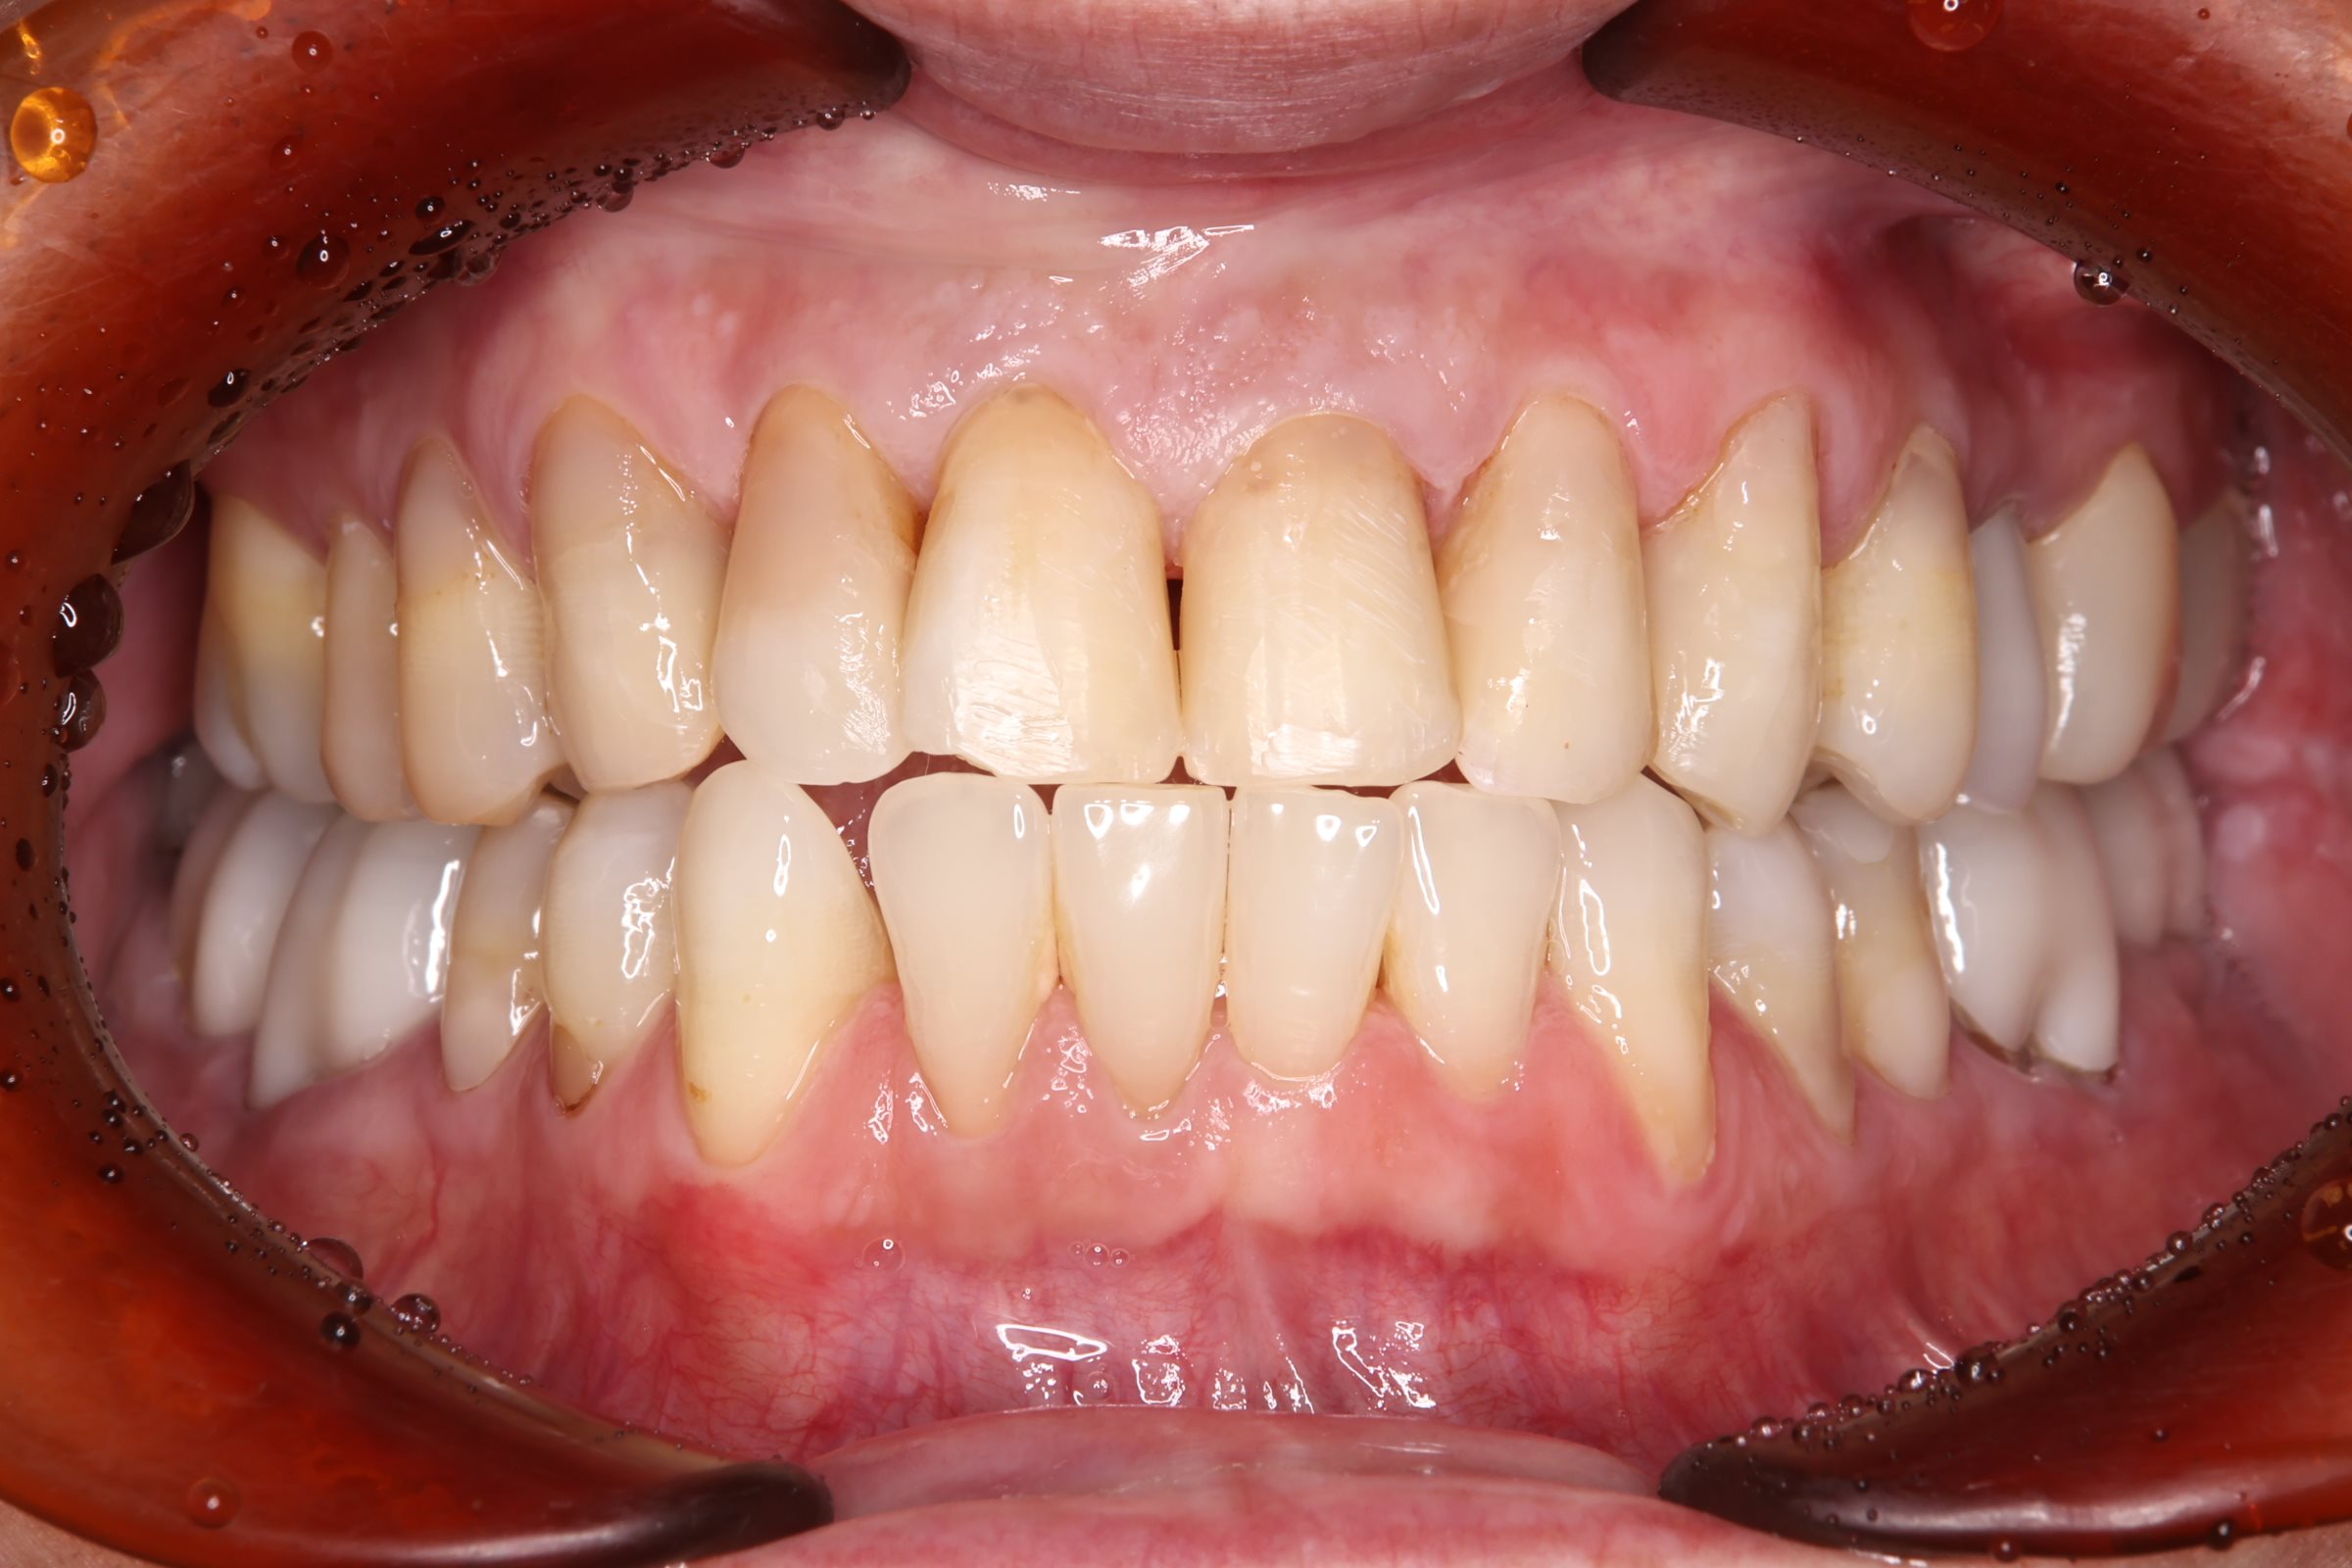

治療結果

銀歯をすべてセラミックへ置き換え、あわせてホワイトニングを行ったことで、口腔内全体が明るく清潔感のあるお口元になりました。また審美的な向上が得られただけでなく、プラーク(細菌)が付着しにくい環境を整えることができた点も大きな成果です。

また、痛みや違和感の原因となっていた部位についても適切な処置を行ったことで、現在は違和感なく、安心して噛める状態が維持されています。

機能面と審美面の両面において、良好な治療結果が得られました。

After